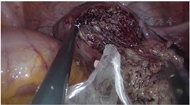

诊治经过:综合病史、体格检查及辅助检查。术前诊断:子宫肌瘤、宫内膜息肉待诊;遂于2020年2月24日行宫腔镜检查及TU-LESS子宫肌瘤挖除术。宫腔镜术中见:两侧宫角及子宫后壁均可见息肉样突起,直径约1 cm,术中冰冻病理结果提示子宫内膜呈增生期组织像。腹腔镜下见子宫增大如孕2个月大小,后壁肌壁间突向浆膜下可见一直径约5 cm×5 cm×6 cm的肌瘤样突起,实性、质软,切面呈灰黄色、未见明显旋涡状结构,与子宫肌壁界限欠清,考虑恶性不能排除,术中及时将标本袋置于瘤体周围继续挖除,以减少病灶在盆腹腔内的播散(图2)。全部标本装袋后于脐部切口经冷刀旋切取出(图3)。术中冰冻病理结果显示高度怀疑子宫内膜间质肉瘤(endometrial stromal sarcoma,ESS)(低级别),待冻后石蜡病理结果确定。术中与患者家属沟通,鉴于患者年轻,且术中冰冻病理与术后石蜡病理结果可能存在不一致,选择暂不扩大手术范围,等待术后石蜡病理结果。